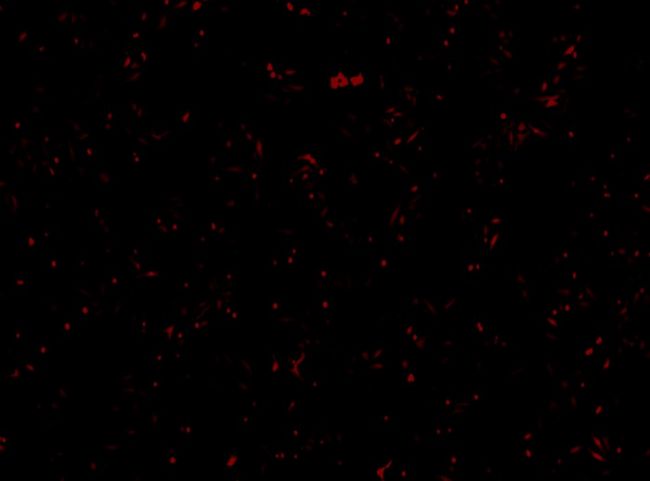

活細胞成像通過實時監測細胞在轉染過程中的動態變化,幫助評估轉染效率、基因表達和細胞健康狀態。在細胞轉染實驗中,利用熒光標記的轉染分子和報告基因(如GFP),可以觀察轉染分子進入細胞、分布及其對細胞功能的影響。此外,活細胞成像還能夠跟蹤細胞存活、增殖、遷移等行為,評估轉染對細胞的生理影響,從而為轉染技術的優化和基因功能研究提供關鍵數據。

| 總細胞覆蓋率(14.1%) |

轉染細胞覆蓋面(6.1%) |

Celloger 活細胞成像監測CHO細胞生長過程